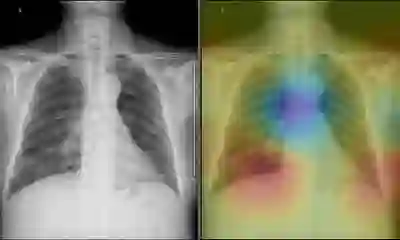

此次推出的10款智能诊断应用,均针对不同的医疗场景和当下亟需解决的医疗痛点。以“智能体检读片”为例,在中国,一家体检中心每天会产生上千例X光胸片,但平均往往只有几十例存在异常,医生要将大量时间精力耗费在逐一阅读健康胸片上。这样不仅医生负担重,患者看病也要耗费更多等待时间。现在,只需在X光设备上安装这款“智能体检读片”智能诊断应用,就能有效解决这一痛点。它如同一位医生的“AI助理”,可快速从海量影像中预筛出健康的X光胸片,只将有疑似疾病的提交医生阅读。

一键自动标注疑似病灶

据联影智能核心团队成员之一郑介志介绍,为了保证这位“AI助理”筛选胸片的精准程度,团队使用了20万个X光胸片数据对其进行深度学习训练。目前,在肺结节、肺水肿、胸膜增厚等14种肺部疾病中,这位“AI助理”已有9种诊断精准度排名世界第一,超过美国国立卫生院、美国斯坦福大学相关研发团队。